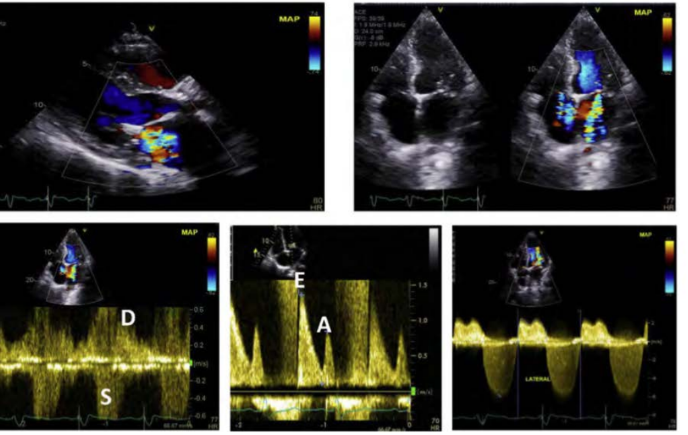

Evaluation of MR: MR jets by TTE is frequently limited by what artifacts from the mitral prosthesis?

MR jets by TTE is frequently limited by acoustic reverberation or shadowing from the mitral prosthesis

Evaluation of MR: what is often the optimal view for evaluation of prosthetic MR jets?

Parasternal window is often the optimal view for evaluation of prosthetic MR jets, PLAX

Apical views may be helpful to identify what for MR?

Apical views may be helpful to identify a suspected eccentric regurgitant jet or

paravalvular regurgitation

for MR, Apical views may also provide better visualization of what 5 things

Apical views mayalso provide better visualization of the prosthetic valve

leaflets for identification of vegetation, thrombus, pannus, or leaflet

degenerative changes

Prosthetic Mitral Valves

Spectral Doppler is key for evaluation of Mitral Prosthesis Regurgitation, name 7 things

what is the CW MR jet look like

How is the mitral E velocity

how is the systemic output and VTI LVOT despite a Hyperdynamic LV

how is the VTI PrMV/VTI Ratio

a large zone of what seen on the LV sie of the mitral prosthesis ****

a what in pressure compared with previous study

flow of the pulmonary veins